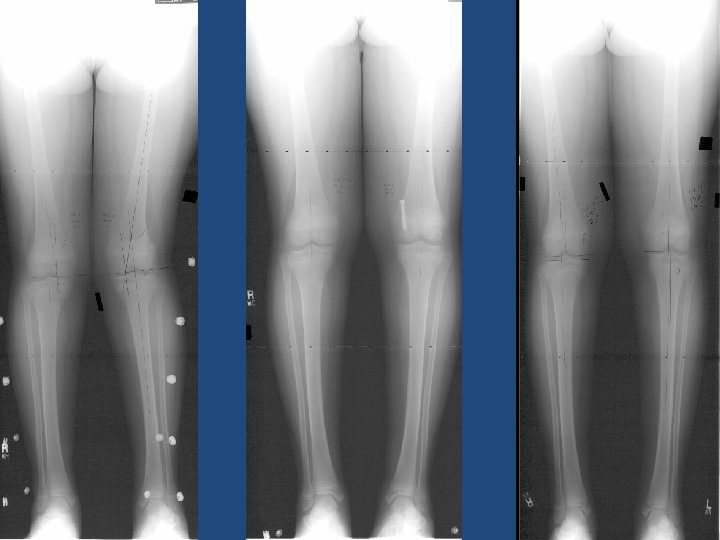

Radiological Parameters Lateral Distal Femoral Angle (LDFA) Medial Proximal Tibia Angle (MPTA) Mechanical Axis (MA) Comprehesive treatment of late –onset tibia vara Gordon JBJS 2005

Genum Valgum 10 -20° of valgus in a patient <10 years of age if line drawn from center of femoral head to center of ankle falls in lateral quadrant of tibial plateau in patient > 10 yrs of age Physeal stapling for idiopathic genu valgum Stevens JPO 1999

Genum Varus if line drawn from center of femoral head to center of ankle falls in medial quadrant of tibial plateau in patient > 10 yrs of age

Leg Length Discrepancy

Concepts…. . Leg Length Discrepancy: 2 cm to 5 cm projected Distal Third Femur: 1 cm by year Proximal Third Tibia: 0. 6 cm by year No more of two years: Permanent Closure By Stages : 2 years / off / 2 years The role of guided growth as it relates to limb lengthening Peter M. Stevens J Child Orthop 2016